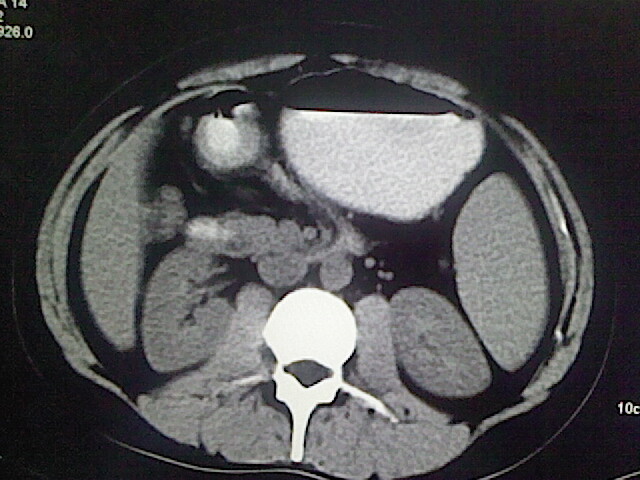

以下是引用卜一在2009-3-14 9:49:00的发言:[br]胆囊萎缩,胆囊壁不规则增厚,内部结构模糊,增强明显强化。另:肝左叶外侧段肝囊肿。支持:慢性胆囊炎!高度可疑:胆囊癌!

以下是引用余辉在2009-3-14 8:48:00的发言:[br]1)慢性胆囊炎。2)肝左叶外侧段肝囊肿。3)脂肪肝。[br]支持,胆囊萎缩,密度增高,不知b超具体有何提示,钙胆汁?结石?

以下是引用jiangjing在2009-3-14 10:18:00的发言:[br]1)慢性胆囊炎。2)肝左叶外侧段肝囊肿。3)脂肪肝。4.】建议行肝功能检查